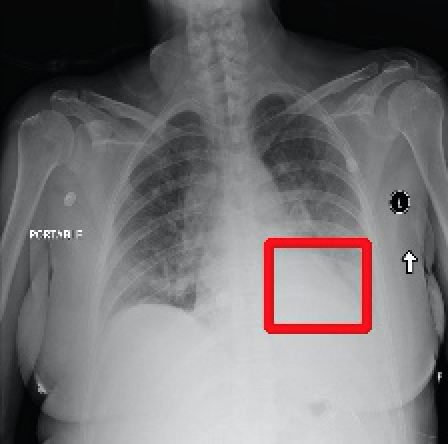

2017年CVPR的一篇“ChestX-ray8”论文[1]首次对医院留存的胸部CT数据库进行人工处理,并通过医学专家分别对8种疾病作标记,形成该领域首个标准的数据库,为胸部医疗的计算机辅助诊断打开了大门,也为后续的研究提供铺垫。CT数据库整理的效果如下图所示,其中红线框内为人工标注的疾病区域:

Atelectasis Cardiomegaly Effusion Infiltrate

Mass Nodule Pneumonia Pneumothorax

图2.1 胸部数据集示例

目前为止,数据集已经达到了14个疾病的分类结果,每张图的大小为1024×1024,少数图片附有由专家标注的病理区域,数据集共有112120张图片,来源于30805个不同的病人,其中51708张图片被标注有疾病,其余则为无病。可以看出无病的数据较多,对有病的特征学习可能较低,相关的学习加速收敛的方法将在2.4节讲解。